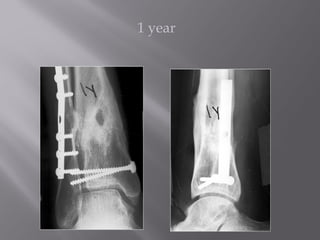

1 year

7 years